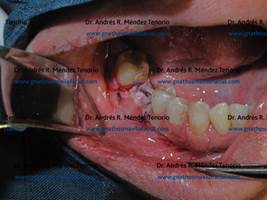

Implante inmediato

Un procedimiento de implante inmediato es aquel en el que se realiza una extracción dental y a continuación se inserta el implante en la misma sesión quirúrgica. Comúnmente se acompaña de colocación de aloinjerto óseo, para rellenar la separación entre las paredes del lecho de la extracción y la superficie del implante. El siguiente es un ejemplo clínico:

| Rx panorámica donde se observa resto radicular de premolar superior derecho junto a una lesión periapical del premolar adyacente | |

| Extracción del resto radicular y eliminación de la infección en periapice del premolar adyacente | |